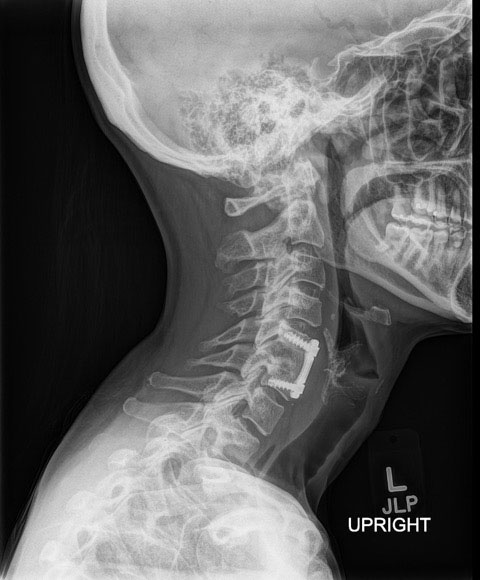

Therefore spinal hardware eg. One of the best signs for pseudoarthrosis failed fusion is a halo formation on the x-ray or CT scan. Finally how well does it work to try a different approach when treating failed fusions.

It has been estimated that about ¼ of patients will have symptoms from problems at an adjacent disc by 10 years after surgery. At C5-6 you have cervical isolated disc resorption which can cause your base of neck and bilateral shoulder pain. If movement remains at the level of the fusion its called a pseudoarthrosis which means a false joint The spine is unstable and may cause problems for the patient.

If there is an issue with your implanted spine hardware your physician will first confirm with an x-ray or other imaging scan. The cause of failed cervical fusion surgery can vary considerably with possibilities that include. If the fusion doesnt happen as it should pseudoarthrosis the screws can loosen.

Pedicle screws may be used as an internal splint to hold the spine while it fuses after spine surgery.